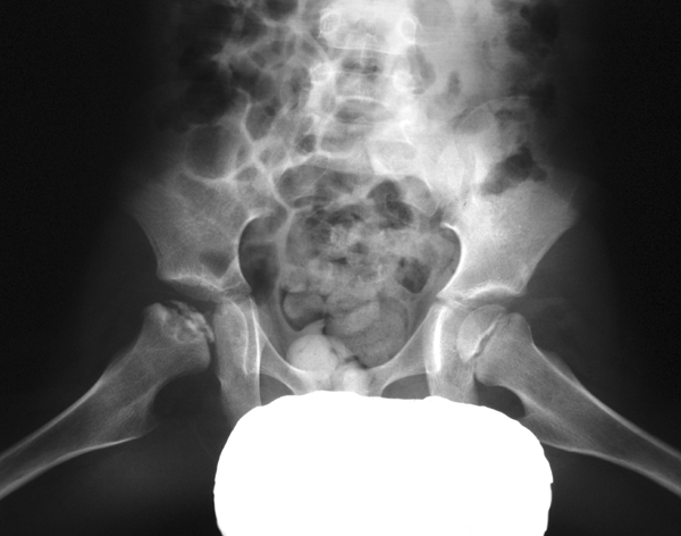

What are the four stages of Legg-Calvé-Perthes disease?

Avascular: ↓ head size, widened joint space. 2. Fragmentation: bone fragments, crescent sign, blurred outline. 3. Repair: revascularization, new bone, wide short neck. 4. Healed/Deformity: flattened, enlarged head, widened neck, enlarged GT.

Radiographic features of Legg-Calvé-Perthes disease?

↓ size, flattened femoral head, ↑ density of epiphysis, widened neck, enlarged GT, low MRI signal.